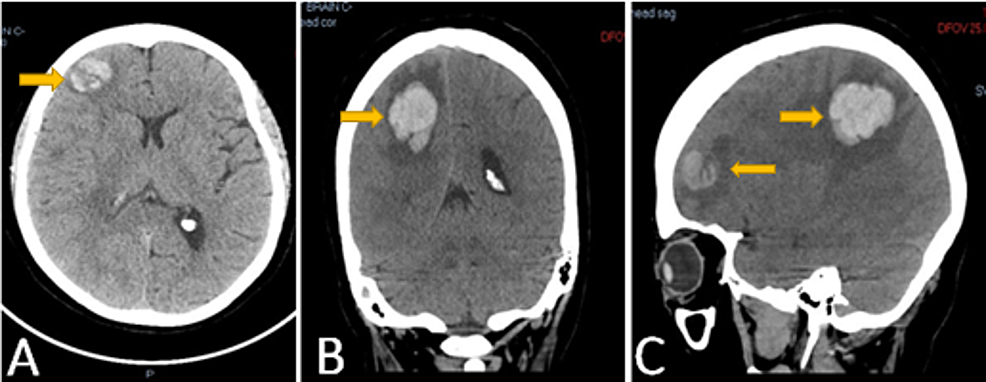

21+ Left Frontal Lobe Brain Tumor Pics. Lobes are large areas of your brain that have a. Problems writing, drawing or naming;

A complete surgical resection can cure both the tumor and the seizures. Cognitive functions are altered by brain. The frontal lobe is separated from the parietal lobe by a space called the central sulcus, and from the temporal lobe by the lateral sulcus.